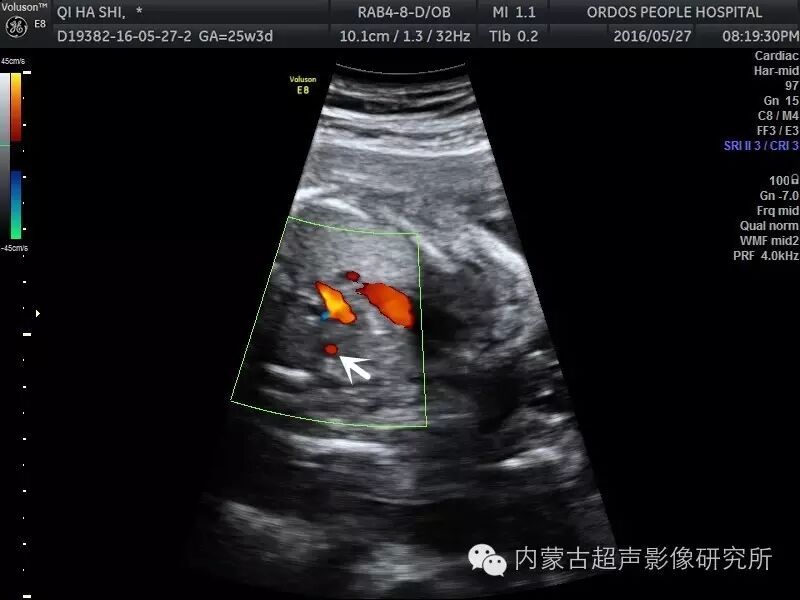

胎儿永存左上腔静脉

胎儿永存左上腔静脉,

1上腔静脉连接及走行异常在胎儿很常见,主要为永存左上腔静脉(plsvc

病例报告:超声诊断胎儿永存左上腔静脉一例

胎儿永存左上腔静脉的超声诊断

永存左上腔静脉